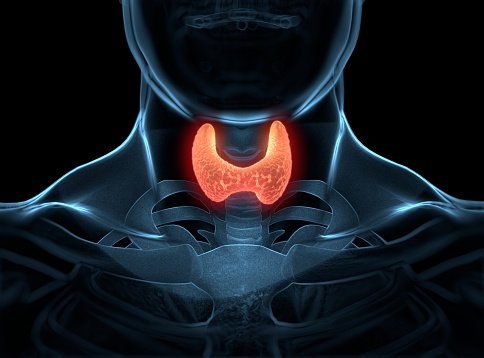

Aunque los beneficios de la terapia con estrógenos en mujeres posmenopáusicas tempranas con una alta carga de síntomas superan los riesgos, este artículo se centra en los tratamientos no hormonales para mujeres que no son candidatas para la terapia hormonal o prefieren evitarla.  JAMA Intern Med, 5 de mayo de 2025.